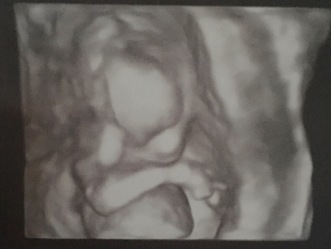

It’s not just the dental 3D scans that interest me though – Richard and I were lucky enough to have a private gender scan of our baby – mostly to satisfy my nosey nature and to confirm my suspicions that the little blob we’d met on week 12 was a baby boy! This too can be done outside the usual hospital setting – we had ours at a small private clinic in Didcot, in a shopping outlet of all places! At the gender scan, we were shown him in 3D, and it was absolutely incredible. Because we could find out near Christmas, we decided to have the scan and open the results on Christmas day – which meant the poor sonographer had to hide his lower half from us! She kept turning the screen on and off to make sure he stayed a surprise – but even without his lower half on the screen, the image was one the best I’ve ever seen. We could make out his little arm moving across his face, rubbing his tiny nose – we saw his little mouth opening and closing – it was just a knock me down with a feather kind of wow. Obviously I wouldn’t imagine everyone to have that kind of reaction to their CBCT scan, although seeing your teeth for the first time in 3D might bring on tears of joy?